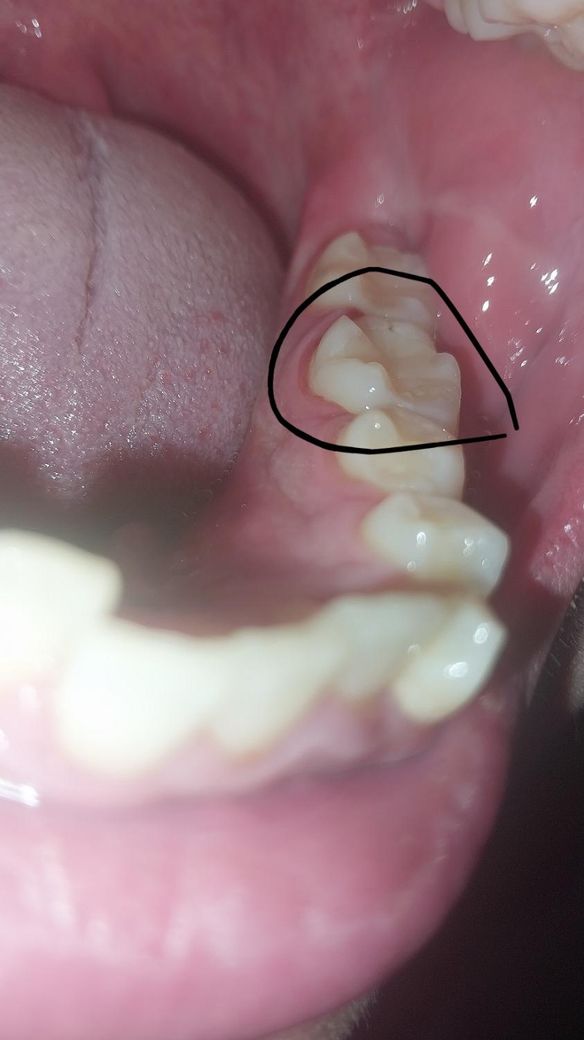

원래 잇몸이 안좋은대... 흠 새벽에 좀 건조한 치간칫솔로 닦으려고 평소처럼 아랫 어금니 사이로 치간칫솔을 넣는데 바로 피가 나서 사진 찍으니 피가 고인건지 피멍이 든건지 어금니 아랫부분이 벌거져서 저렇게 되어버렸습니다... 제가 잇몸이 원래 안좋아서 반년마다 잇몸치료도 받는중인데.. 그냥 치실이랑 치간칫솔 평소처럼 쓰면 될까요? 거울로 자세히 보니 치아 밑으로 핏기가 띠처럼 둘러서 보이는데 칫솔이나 치실등으로 문질러 보니 더이상 피가 나오진 않아요

사진상으로 문제가 잇어 보이진 않고 치실을 과하게 하면 일시적으로 잇몸에 발적이 생길수 잇습니다.

잇몸 사이보다 큰 치간칫솔을 사용하면 잇몸에 상처가 생길수 있습니다.

잇몸의 상처는 대부분시간이 지나면서 줄어들게 되며 치아 사이 공간에 맞는 치간칫솔을 사용하는것이 좋습니다

잇몸이 염증때문에 좀 부어있네요 잇몸 염증은 전신 건강상태에 따라 일시적으로 악화되기도 합니다

잇몸에 좋은 생약성분치약쓰시고 컨디션 관리해두세요